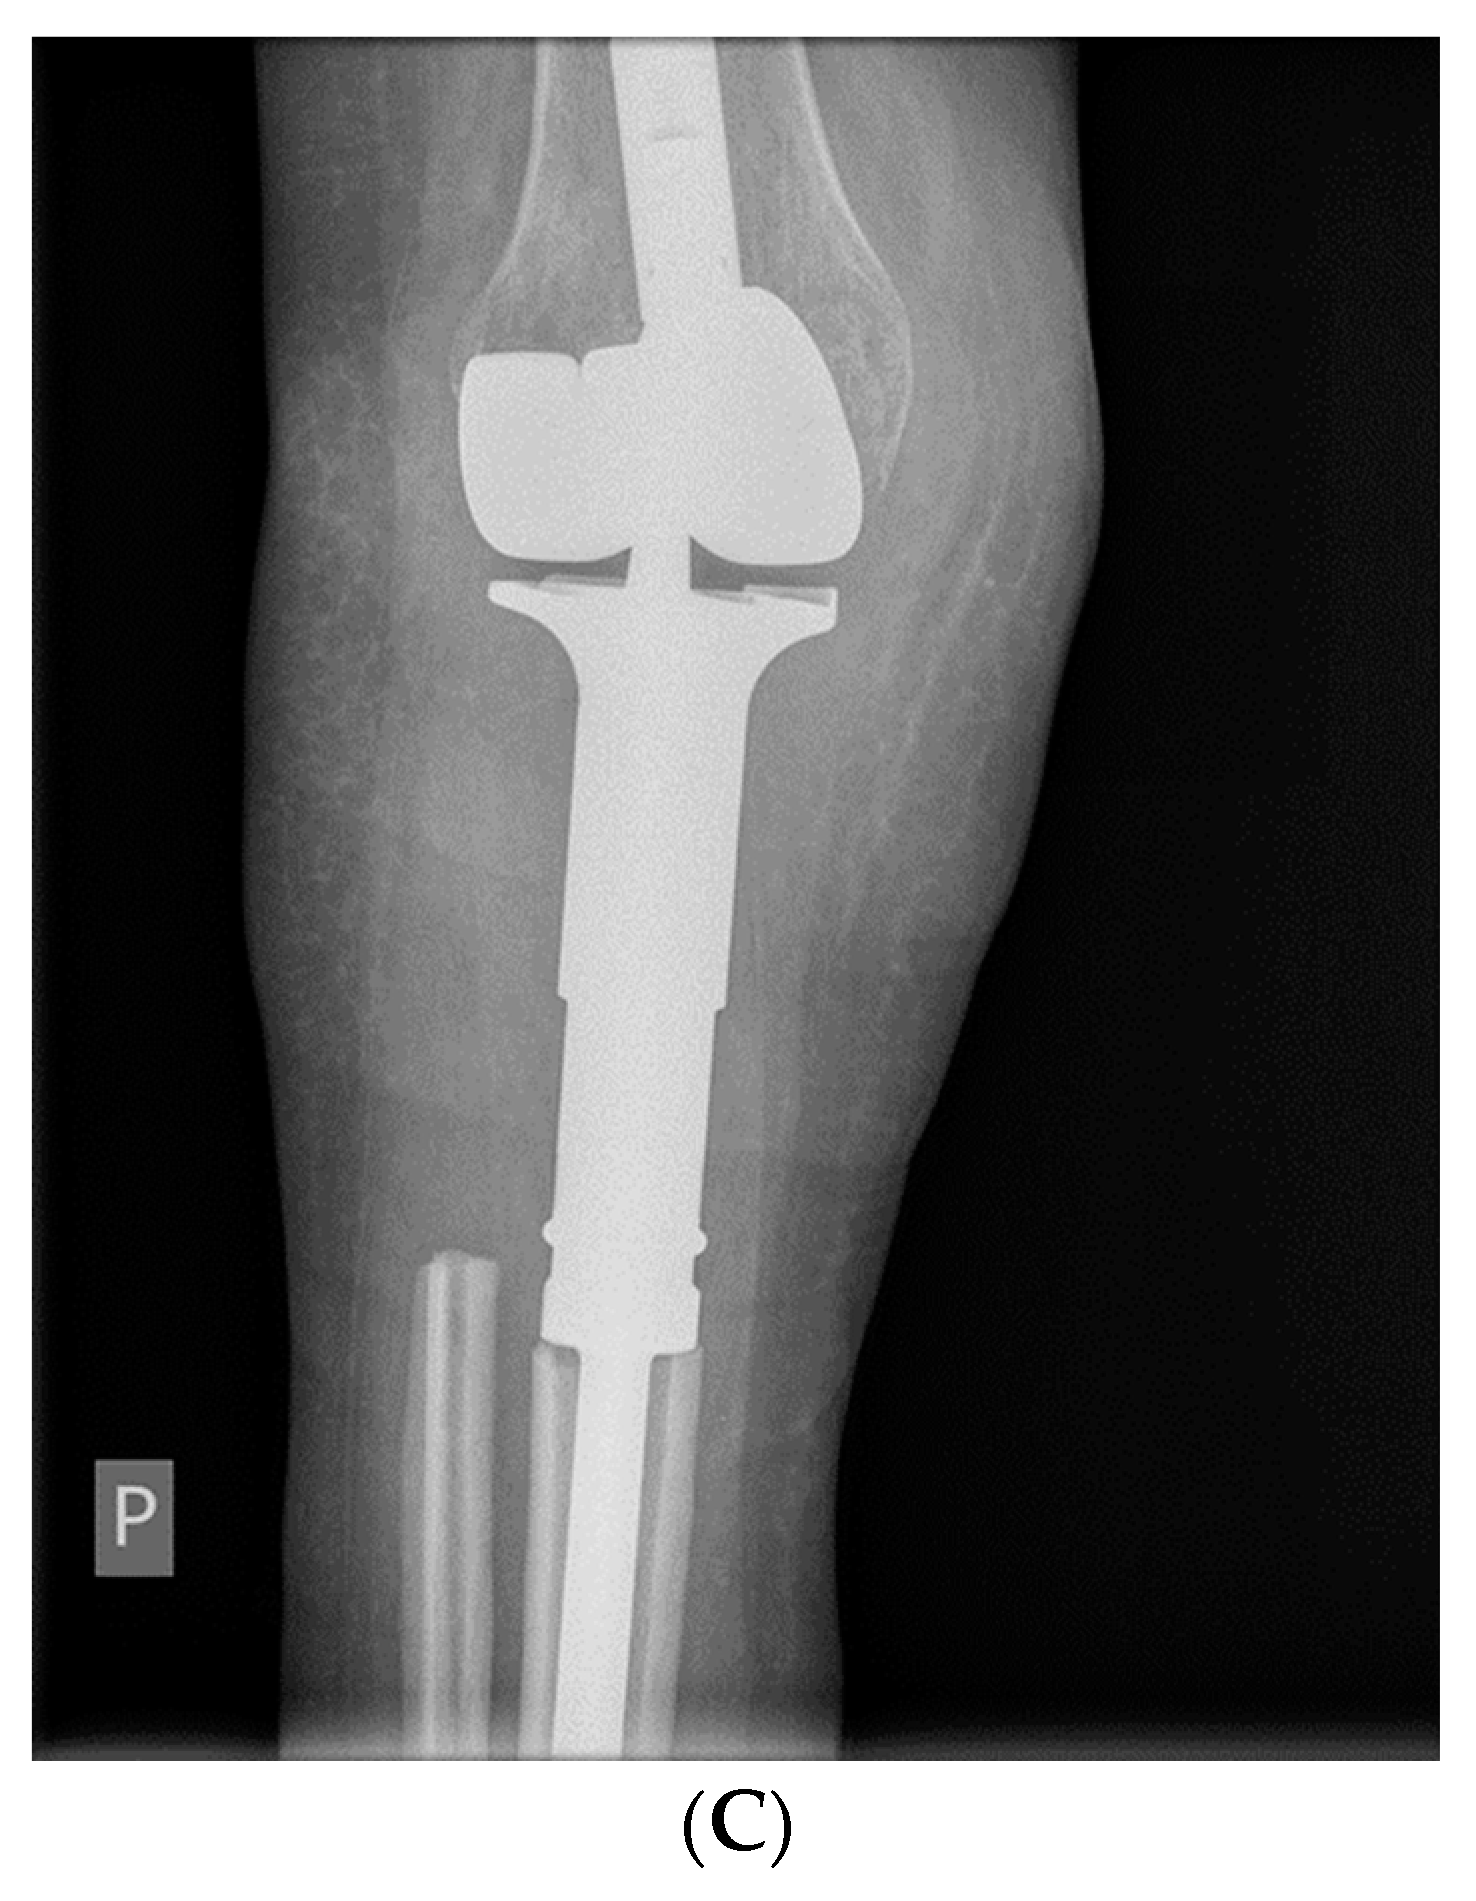

- McCarthy, C.L.; Gibbons, C.L.M.H.; Bradley, K.M.; Hassan, A.B.; Giele, H.; Athanasou, N.A. Giant cell tumour of the distal radius/ulna: Response to pre-operative treatment with short-term denosumab. Clin. Sarcoma Res. 2017, 7, 19. [Google Scholar] [CrossRef]

- Hakozaki, M.; Tajino, T.; Yamada, H.; Hasegawa, O.; Tasaki, K.; Watanabe, K.; Konno, S. Radiological and pathological characteristics of giant cell tumor of bone treated with denosumab. Diagn. Pathol. 2014, 9, 111. [Google Scholar] [CrossRef]

- Van Langevelde, K.; McCarthy, C.L. Radiological findings of denosumab treatment for giant cell tumours of bone. Skelet. Radiol. 2020, 49, 1345–1358. [Google Scholar] [CrossRef] [PubMed]

- Oguro, S.; Okuda, S.; Sugiura, H.; Matsumoto, S.; Sasaki, A.; Susa, M.; Morioka, H.; Jinzaki, M. Giant Cell Tumors of the Bone: Changes in Image Features after Denosumab Administration. Magn. Reson. Med. Sci. 2018, 17, 325–330. [Google Scholar] [CrossRef]